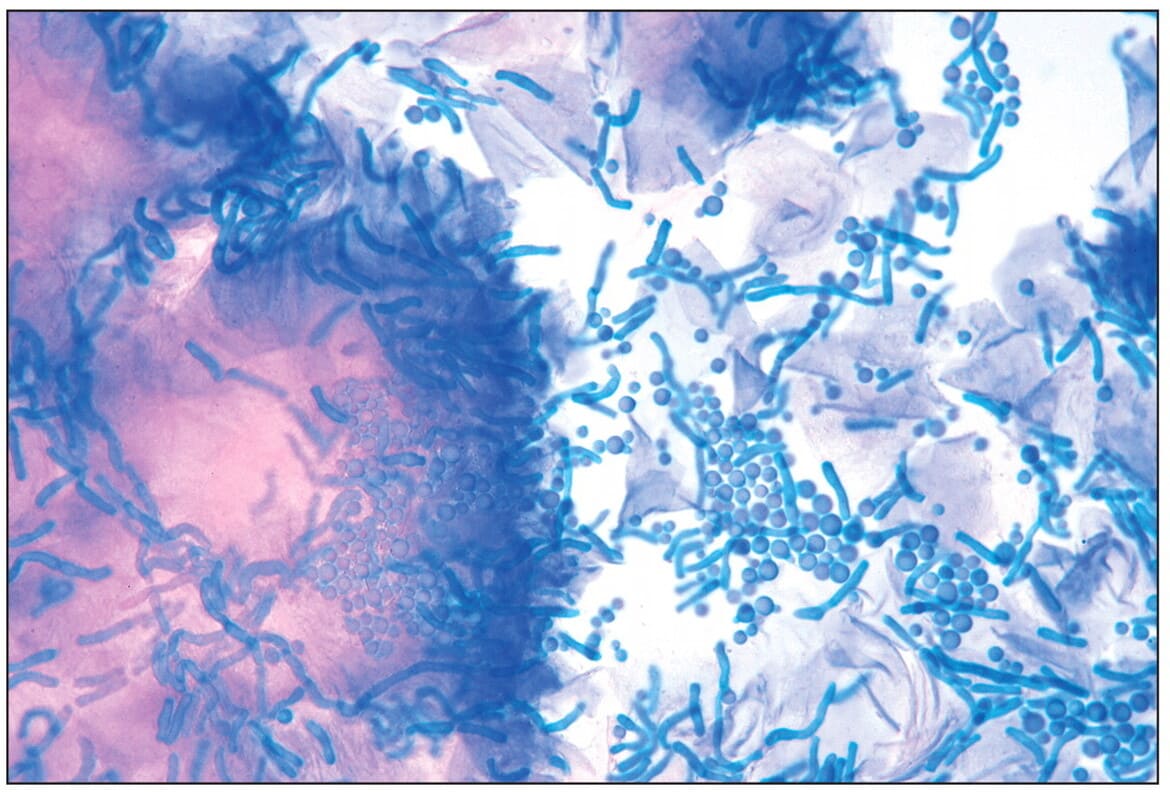

Почему появляется перхоть на голове

Перхоть — образование на коже головы чешуек (мёртвых клеток) белого или желтоватого оттенка. Считается одной из лёгких форм себорейного дерматита.

Главные причины появления:

- избыточное размножение грибка Malassezia Furfur и Pityrosporum ovale;

- эндокринные заболевания, нарушение обмена веществ (например, сахарный диабет);

- гормональные изменения во время беременности, пубертатного периода, при приёме антибактериальных средств, оральных контрацептивов;

- перенесённое ранее ОРВИ;

- авитаминоз (нехватка цинка, селена, витаминов А, В, С, Е);

- заболевания желудочно-кишечного тракта;

- неправильное питание;

- сильные стрессы;

- поражение ЦНС (парез мимических мышц, болезнь Паркинсона).

На заметку! Перхоть усиливается зимой, при сухой и холодной погоде. Спровоцировать появление чешуек можно также чрезмерным использованием укладочных средств, косметики с агрессивными ПАВами в составе, постоянным вытягиванием волос плойками, чрезмерным пересушиванием феном, слишком частым или, наоборот, редким мытьём головы.